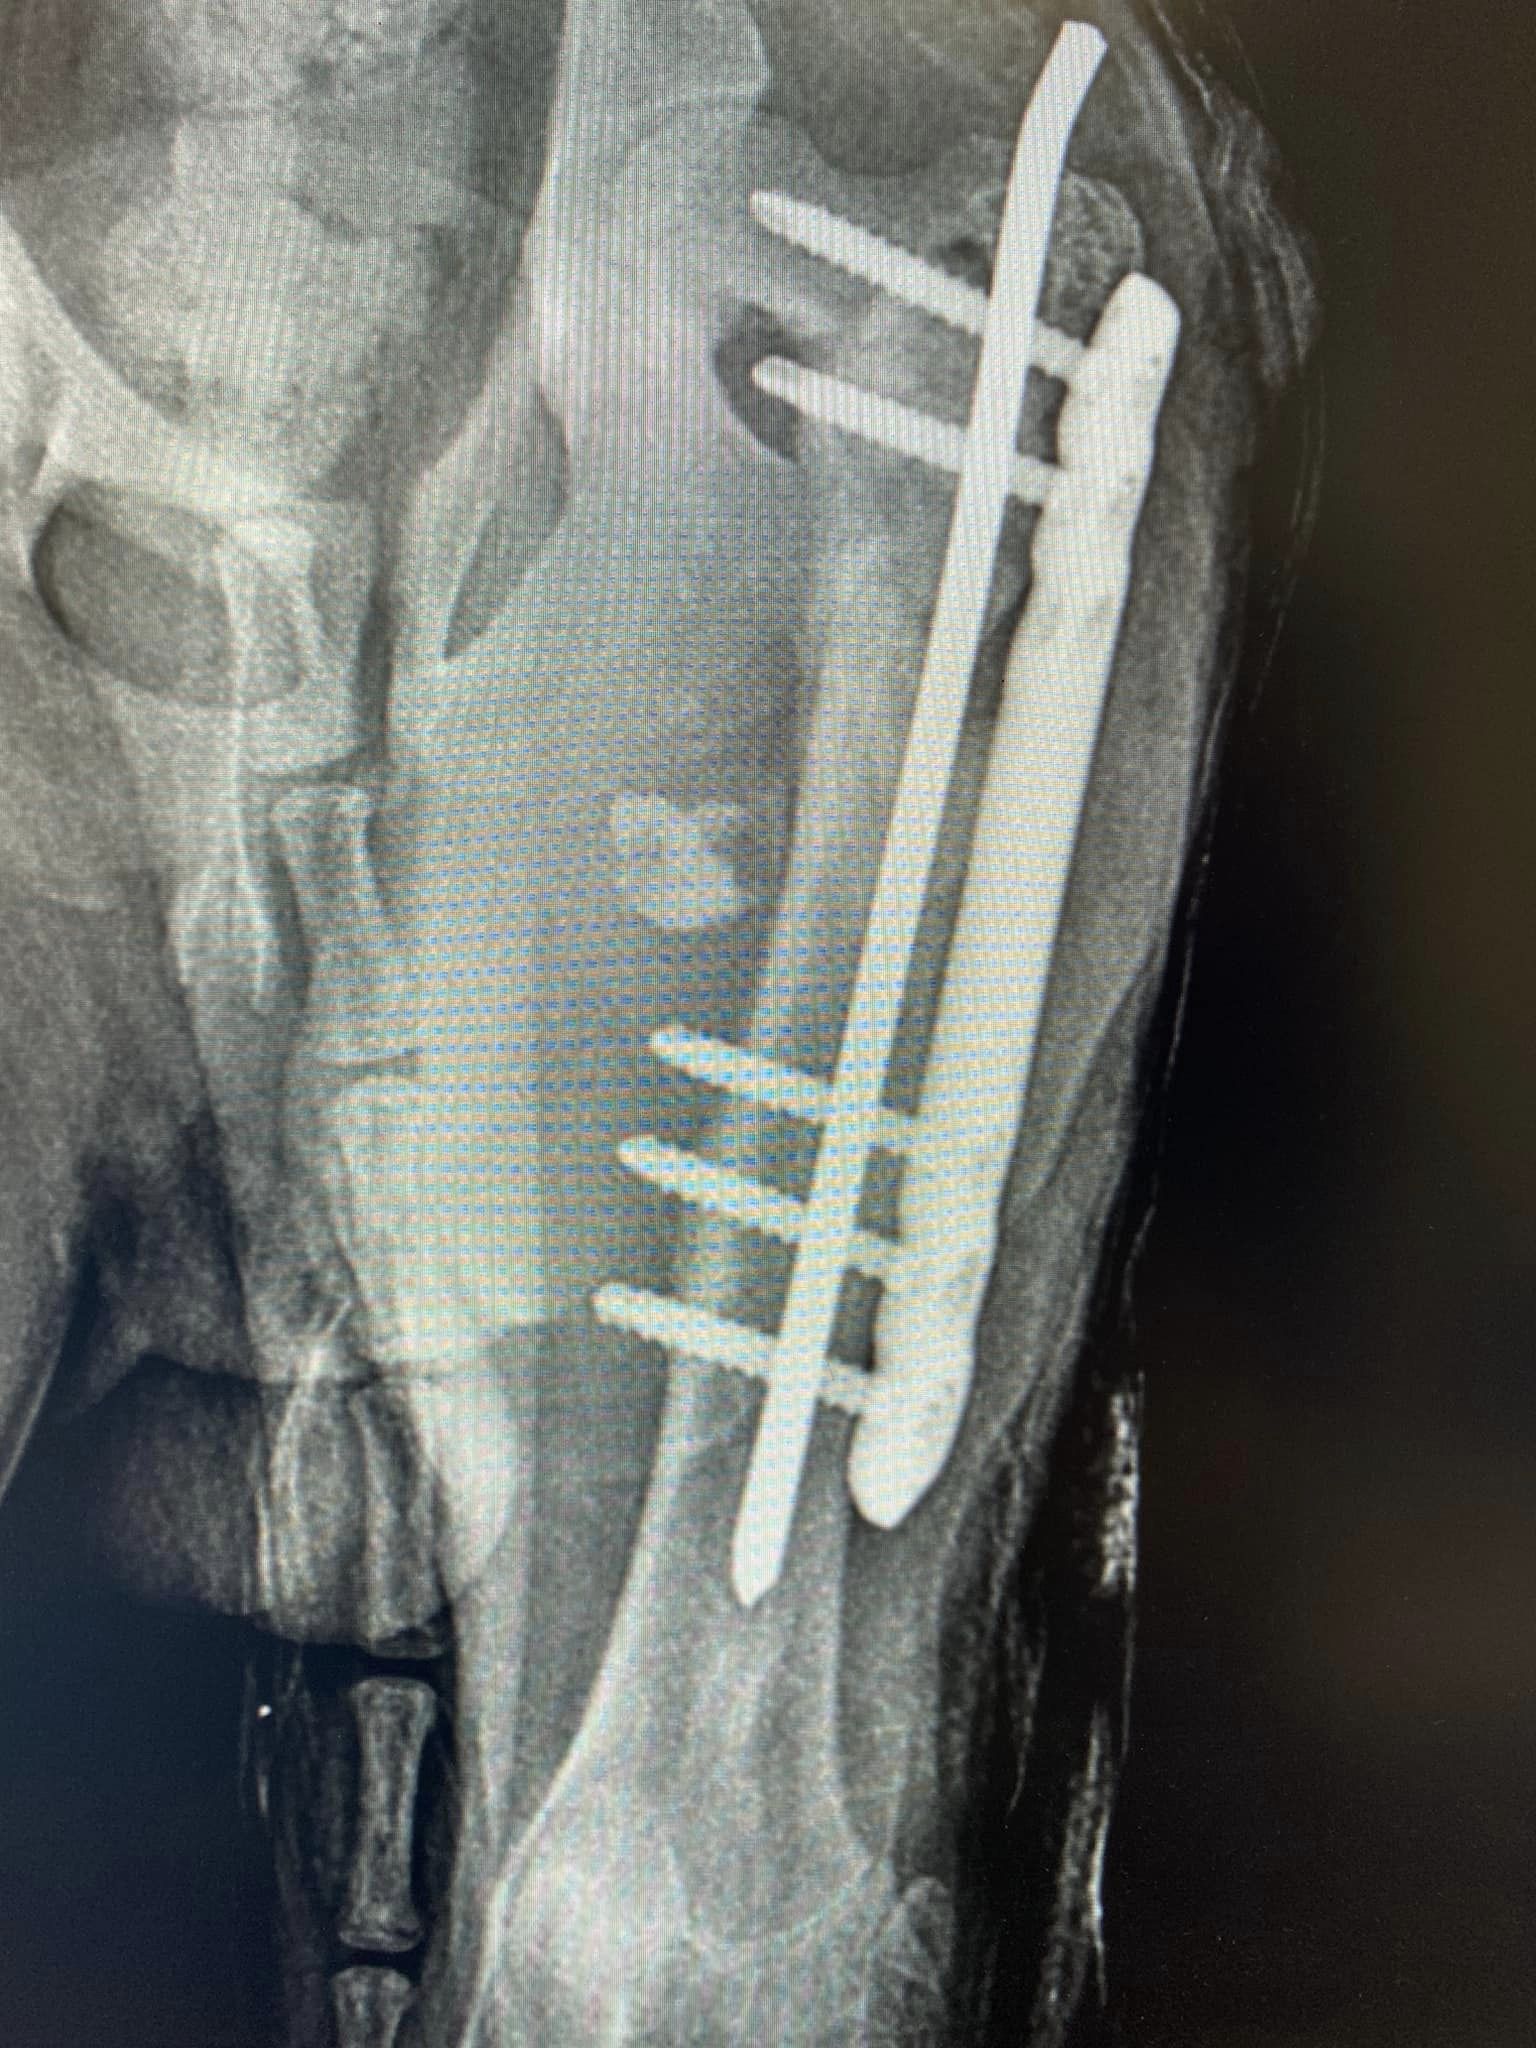

Zastosowanie płyty mostującej 1 lutego 202318 grudnia 2023 Zastosowanie naszej płytki mostującej, cieszy bardzo! Pozdrawiamy specjalistów z Przychodnia weterynaryjna „Kiełbowicz” ! Śledź nas na: